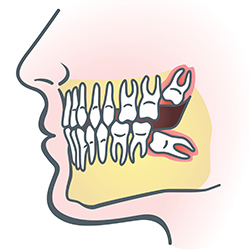

Wisdom Teeth

wisdom teethWisdom teeth are types of molars found in the very back of your mouth. These teeth usually appear in late teens or early twenties but may become impacted (fail to erupt) due to lack of room in the jaw or angle of entry. When a wisdom tooth is impacted, it may need to be removed. If it is not removed, you may develop gum tenderness, swelling, or even severe pain. Impacted wisdom teeth that are partially or fully erupted tend to be quite difficult to clean and are susceptible to tooth decay, recurring infections, and even gum disease.

Wisdom teeth are typically removed in the late teens or early twenties because there is a greater chance that the teeth's roots have not fully formed and the bone surrounding the teeth is less dense. These two factors can make extraction easier, as well as making the recovery time much shorter.

In order to remove a wisdom tooth, your dentist first needs to numb the area around the tooth with a local anesthetic. Since the impacted tooth may still be under the gums and imbedded in your jaw bone, your dentist will need to remove a portion of the covering bone to extract the tooth. In order to minimize the amount of bone that is removed with the tooth, your dentist will often "section" your wisdom tooth so that each piece can be removed through a small opening in the bone. Once your wisdom teeth have been extracted, the healing process begins. Healing time varies depending on the degree of difficulty related to the extraction. Your dentist will share with you what to expect and provide instructions for a comfortable, efficient healing process.